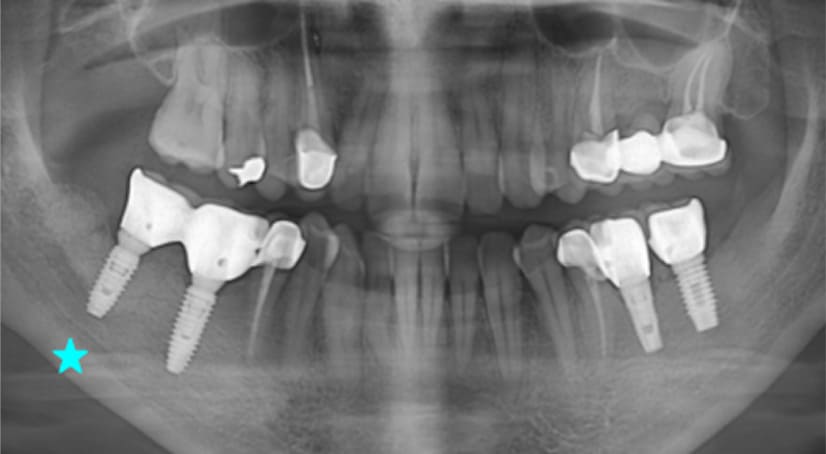

13+ 年

-

种植体植入:2012 年 9 月 -

最终修复体:2013 年 1 月 -

随访:13 年(2025 年 1 月)